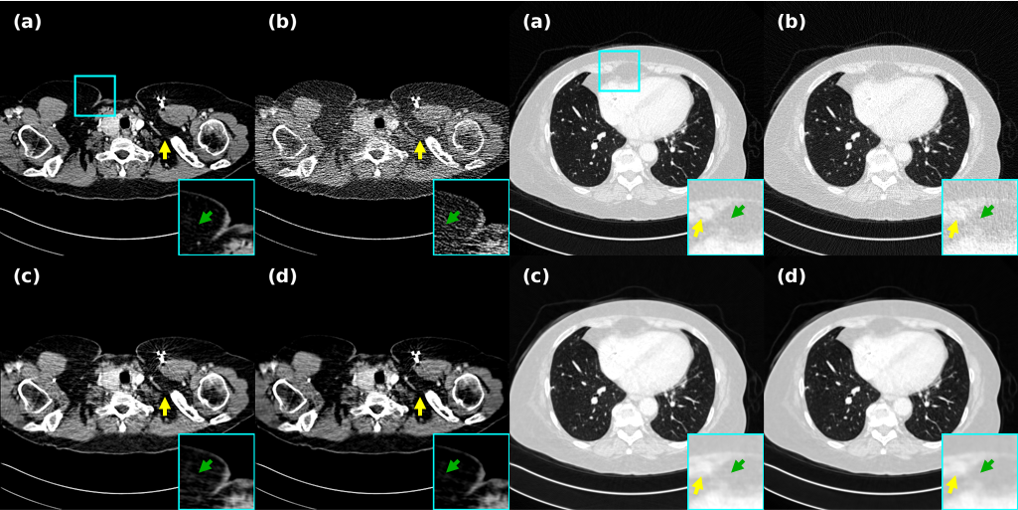

In this study, the superiority of the present model is demonstrated by quantitatively evaluating the Mayo and LIDC-IDRI datasets with dose, respectively. In the other experiments of the comparison, we have taken the traditional method, self-supervised and clean data based iterative diffusion method, which can reflect the advancement of the present method from several angles, which is clearly demonstrated in Fig. 5 from the image itself, zoomed-in and residual maps. The traditional TV, although it can realize the noise removal, has transitional smoothing and destruction of pathological features, and the parameter settings are non-uniform for different data and system devices. Deep learning-based methods, such as B2U, suffer from performance degradation due to their inability to adapt to the overly structured and correlated noise in CT images. Noiser2Noise tends to introduce too much random noise due to the introduction of additional noise in the noisy image itself in order to construct a supervised image, appearing to smooth out textures and details similar to TV methods. In addition, Prompt-SID, which is based on cue learning and introduces a diffusion model to amplify the perceptual noise, did not show eye-opening results on the Mayo dataset. NBR, which fails to introduce enhancement for similarity as our method, produces lesions that do not stand out as shown in Figs. 5 and 6, both in the lungs and in the abdomen. As can be seen from Table 1, Noise2Sim, AdaReNet, and IPDM all showed good results, but Noise2Sim’s method based on batch data similarity requires higher data z-axis orientation, which resulted in a significant drop in metrics across different datasets, and the overly randomized selection of similar data can easily lead to drifting of CT values as shown in Figs. 5 and 7. However, our method mitigates the CT value mismatch due to the pixel-level weighted correction that achieves a balance in suppressing noise and preserving details. Notably, although the effect on the LIDC data is lower than that of AdaReNet, it requires independent noisy data with the same information, which cannot be strictly classified as self-supervised, and as shown in Fig. 7, the image produces a smoothing of the details on the muscle tissues and bones, which can interfere with the diagnostic performance of the radiologist to a large extent. For IPDM’s approach based on iterative diffusion over two domains starting from clean data, which mitigates the presence of noise at the cost of a huge cost, although modeling with clean data has a great advantage, it is still not sufficient for feature recovery. As shown in the folded line in Fig. 5, our method is closest to the reference in terms of amplitude variation, which fully demonstrates the robustness of the present method in denoising reconstruction. In addition, it is worth emphasizing that our method only requires single LDCT projection data, whether training or testing the model, which is a real self-supervised method that this study aims to address when a large number of labels are missing in the clinic.